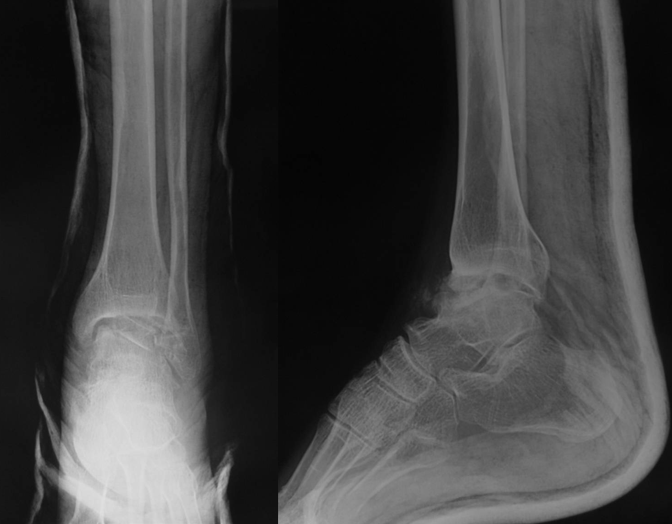

王岩  男  24岁

软组织撞击

术后复查